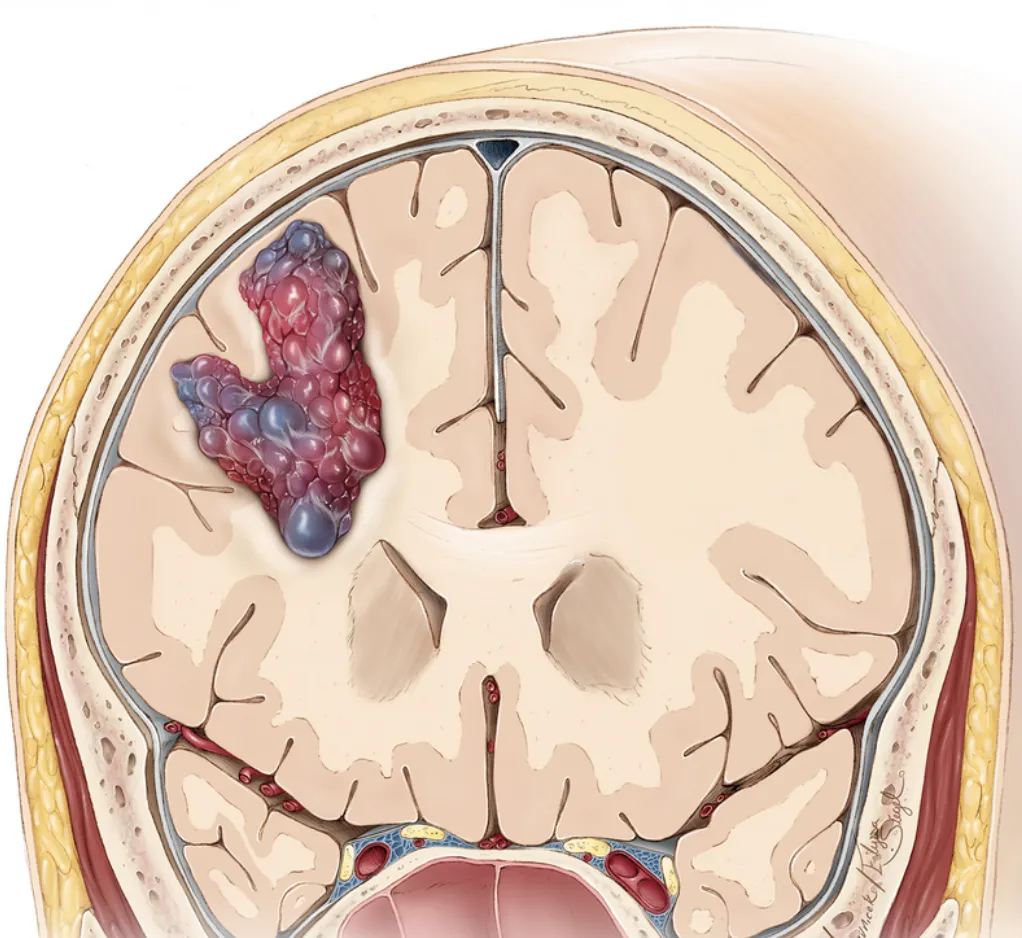

脑海绵状血管瘤是一种由异常血管组成的良性病变,这些血管壁薄且缺乏正常的血管结构,容易出血或形成血栓。与动静脉畸形(AVM)等其他脑血管疾病不同,海绵状血管瘤的血管团块内没有动脉成分,因此其血流速度较慢,出血风险相对较低。然而,一旦出血,仍可能对周围脑组织造成严重损害。海绵状血管瘤可以发生在身体的任何部位,但最常见于脑部和脊髓。根据病变的位置和大小,患者的症状和预后也会有所不同。

海绵状血管瘤MRI(图源见水印)